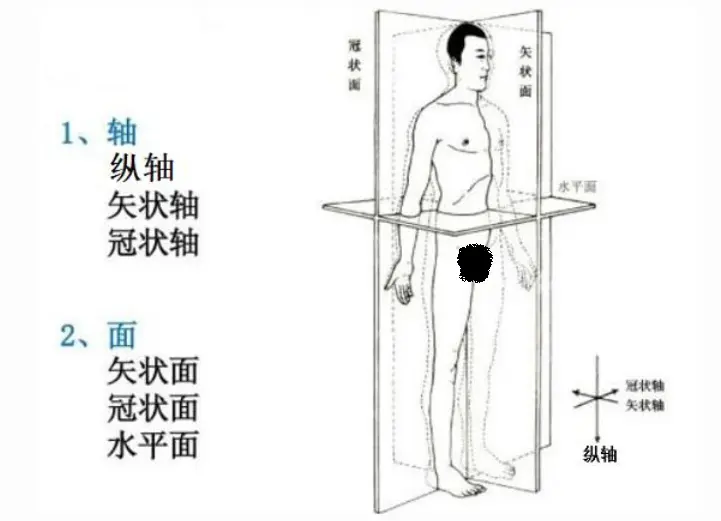

还是先从最基础的一些解剖学术语开始吧,在解剖中立位上,肢体沿矢状面向前动作为屈曲,向后为伸展(膝关节相反)。沿冠状面向左右两边分开为外展,向中间靠拢为内收。沿水平面动作为旋转。